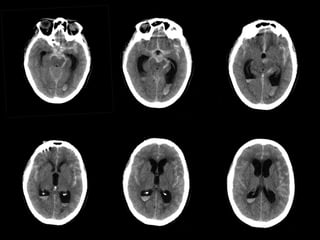

Modifications Modifications Microangiopathiques Microangiopathiques  Vous pourrezvoirle terme Vous pourrez voirle terme “modifications microangiopathique” “modifications microangiopathique” ou Leucoaraïose dans les rapports ou Leucoaraïose dans les rapports  Ils se refèrent à des ischémies de la Ils se refèrent à des ischémies de la substance blanche par maladie des substance blanche par maladie des petits vaisseaux due à l’âge petits vaisseaux due à l’âge  Trés souvent rencontré aux âges Trés souvent rencontré aux âges avancés avancés  Sa signification clinique est encore Sa signification clinique est encore inconnue inconnue Modifications Microangiopathiques Normal